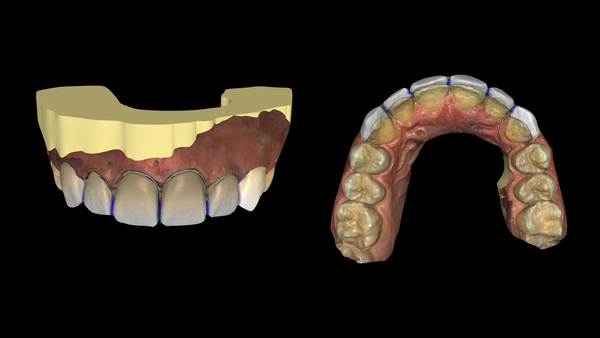

Fig. 6. Pianificazione dei restauri in CAD.